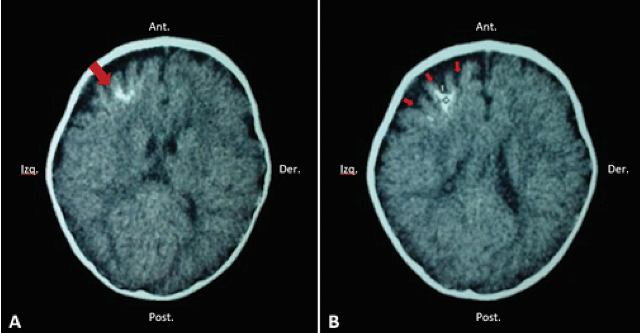

It can be diagnosed by the finding of typical clinical symptoms and by the facial appearance of the port-wine stain 11. ?All patients with facial nevus should undergo radiological evaluation to rule out SWS?, which can be helpful in detecting the classic intracranial calcifications in these patients 1 ( Figure 2).

However, multiple radiological findings have been seen such as atrophy of cerebral lobes, hypertrophy of choroid plexuses, enlargement of deep cerebral veins, venous drainage abnormalities and recently an asymmetric enlargement of the cavernous sinus has been described 4, 24( Figure 3).